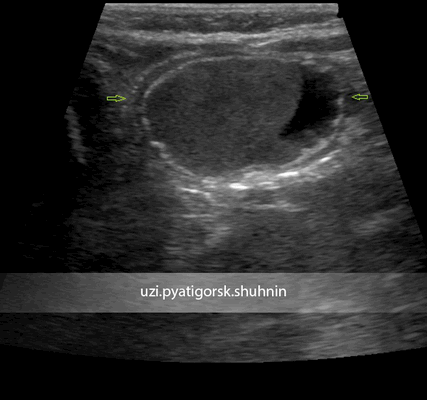

УЗИ брюшной полости ребенка 3-х месяцев. Направлен с диагнозом «киста правого яичника». При исследовании выявлено кистозное образование, прилежащее к поверхности правого яичника, но не исходящее из него, со специфическим строением стенки, с негомогенным жидкостным содержимым. Диагноз кисты яичника исключен, установлен диагноз энтерокистомы. Пациентка направлена на консультацию хирурга. Своевременная и верная диагностика позволила уберечь ребенка от возможного негативного сценария развития этого заболевания.